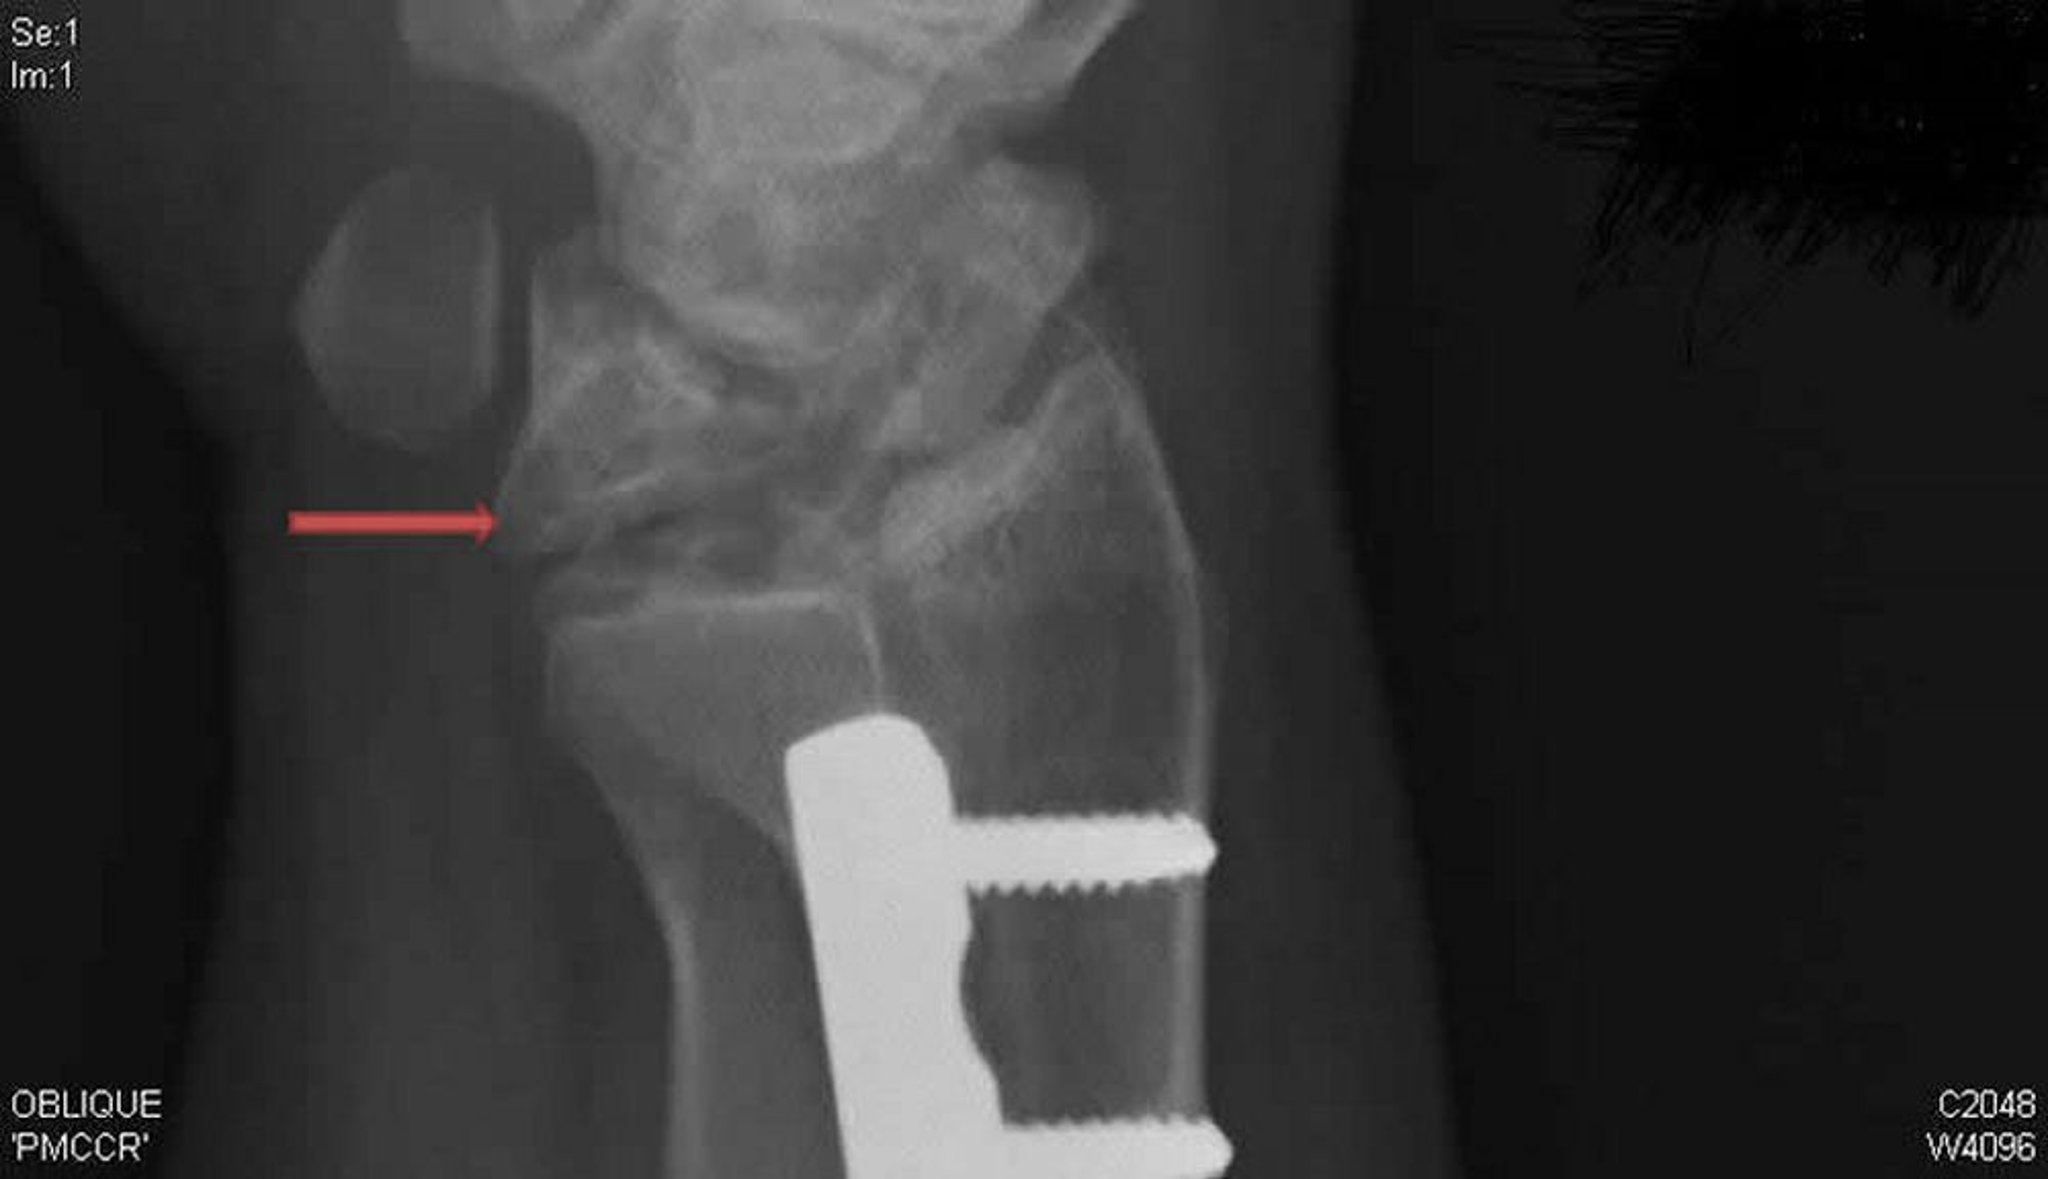

Болезнь Кинбека (косая проекция рентгенографии)

Данная косая проекция при рентгенографии правого запястья указывает на болезнь Кинбека. Обратите внимание на коллапс и фрагментацию полулунной кости (стрелка), которые не были заметны при рентгенографии в задне-передней проекции.

Рентгенограмма предоставлена Давидом Р. (David R.). Steinberg, MD.